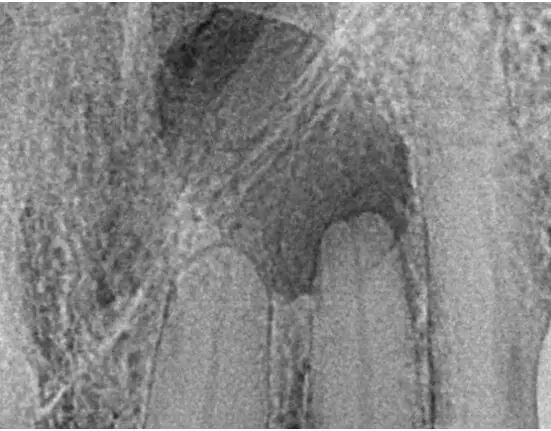

A patient came to my office complaining of a lump on his palate. In the past, I would have taken a 2D x-ray and referred him to my endodontist. Periapical radiographs are only 26% to 48% accurate in diagnosing a periodical lesion (Figure 1).1

However, CBCT is more accurate than periapical radiographs in revealing periapical pathosis.2,3 CBCT is also more accurate than periapical radiographs in identifying apical periodontitis, especially when lesions are greater than 1.4 mm.2,3 CBCT, with its high specificity and accuracy, can enhance pre-op diagnoses as well as post-op evaluation of treatment.

The 2D image showed a lesion, but it did not define the buccal/lingual extent the lesion had progressed. With multiple 3D slices, the true nature of the lesion could be defined (Figures 4, 5, and 6). The 3D rendering of where the lesion had erupted through the lingual wall provided a comprehensive visual for diagnosis (Figure 2 again).